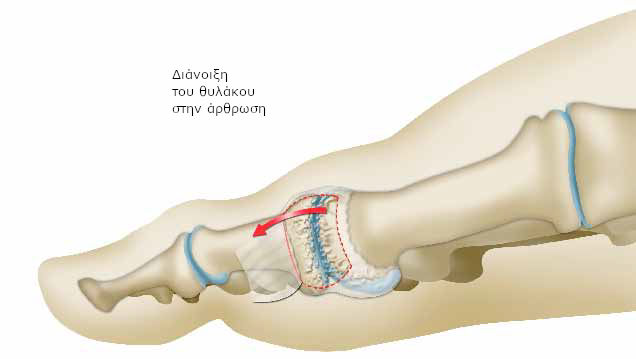

Αρχικά, πραγματοποιεί τομή στον ινώδη σάκο που περιβάλλει την άρθρωση (αρθρικός θύλακος) σε συγκεκριμένο σημείο.

Αφαιρεί, στη συνέχεια, το φθαρμένο χόνδρο της φάλαγγας και καθαρίζει το οστό από προεξοχές.

Τέλος, τοποθετεί και συρράφει το θύλακο με τέτοιο τρόπο, ώστε να αντικαθιστά το φθαρμένο χόνδρο.

Δημιουργείται, με αυτό τον τρόπο, ένα είδος τεχνητής άρθρωσης.